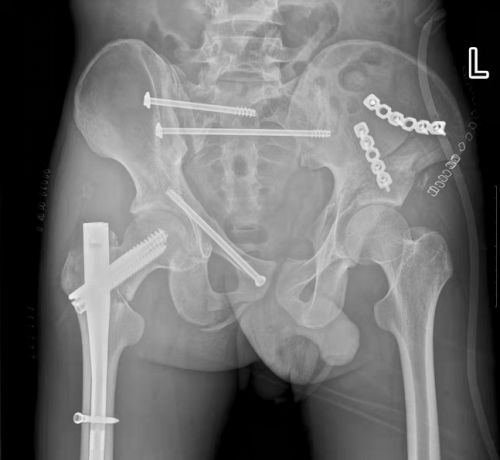

术后,骨折断端固定牢靠。

经过反复讨论研究手术方案,在麻醉科、手术室的配合下,盛斌主任带领创伤救治团队为小张施行复杂骨盆及股骨骨折微创复位内固定手术。术后,在急诊ICU等多学科团队的积极治疗和精心护理下,患者病情好转出院。

盛斌主任指出:相较于传统骨盆修复手术,微创手术不仅对患者的创伤更小、手术风险更低、术后恢复更快、预后更好,治疗费用也更低,深受患者好评。